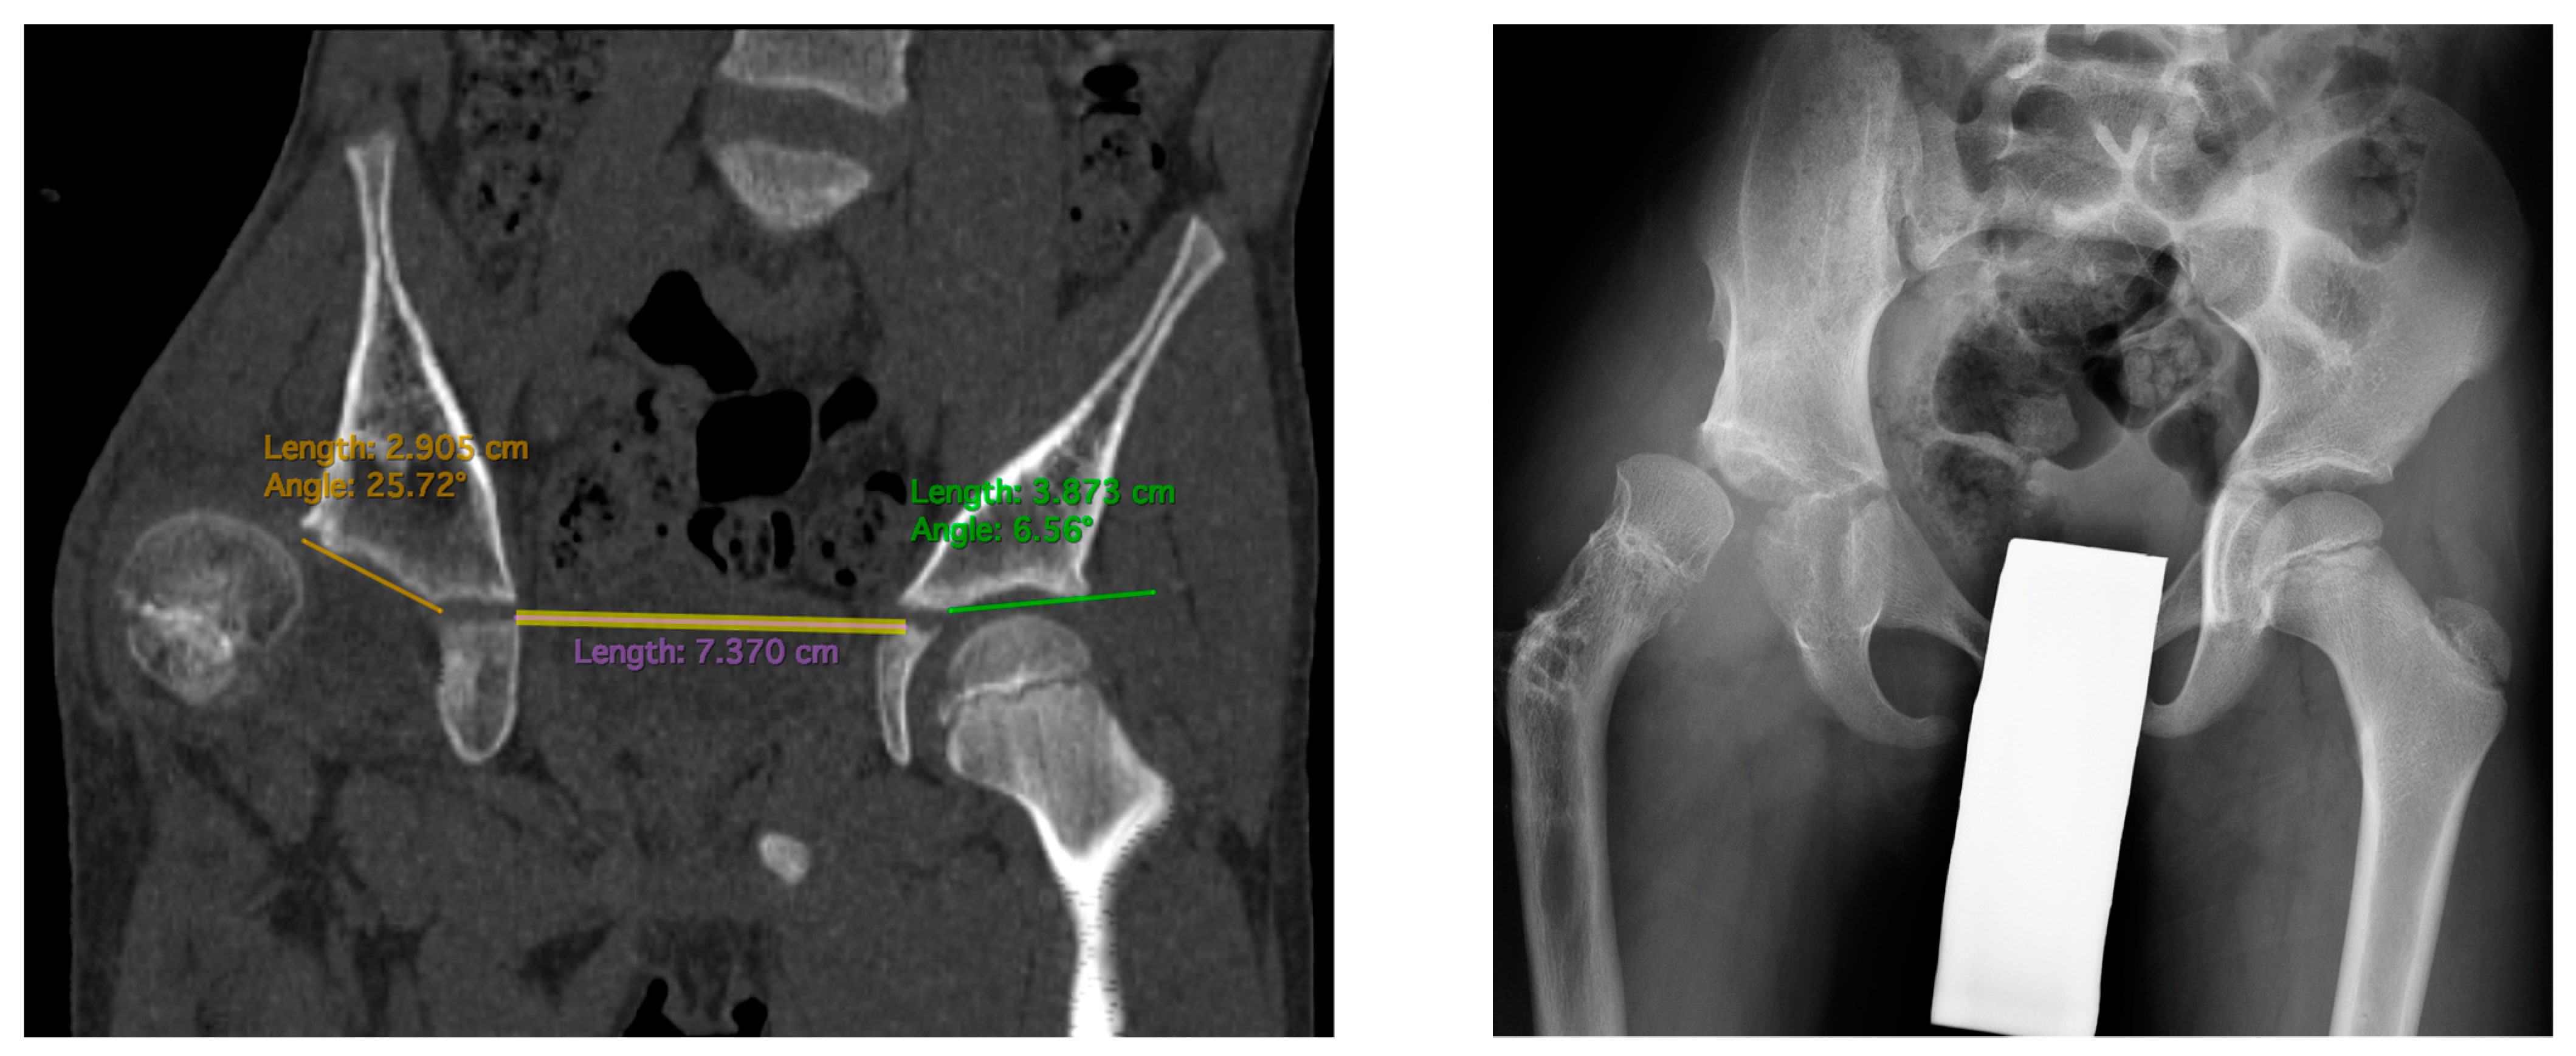

The study is a retrospective cohort review. We have reviewed medical histories and radiograms. The patients were examined three times: (1) before hip reconstruction surgery, (2) before femoral lengthening, and (3) at follow-up. The patients underwent standard AP hip joints radiograms, internal rotation hip radiograms, Rippstein position radiograms [21], and standing lower limbs AP long cassette radiograms. We have measured the Center-Edge Angle (CEA, Wiberg), the Acetabular Inclination (AI), the Neck-Shaft Angle (NSA), and the Antetorsion Angle (AT), and the Shenton line was also evaluated [22,23,24,25,26,27]. Femoral torsion normal values were adapted from the Tönnis study [23], femoral retrotorsion was accepted as a negative true AT value, and diminished AT was accepted as <20 deg. Computed Tomography (CT) scans were available in all 6 patients with hip instability. The following parameters were measured on CT scans [18,28,29,30]: Acetabular Anteversion (AA), Axial Acetabular Index (AAI), and Acetabular Inclination in the anterior (AIa), middle (AIm), and posterior (AIp) part of the acetabulum. CT scans with plane presentation and measurements are shown in Figure 2 and Figure 3. Statistical analysis was performed with the use of STATISTICA v13.3 and PQStat v1.8.4. Significance was determined as p < 0.05.

Figure 2.

CT examination of patient with right hip dislocation. Left: transverse view, right: coronal view. Evaluation of medial (first row), posterior (middle row), and anterior (last row) parts of the acetabulum.

Figure 3.

CT scan showing AIm measurements (left): 24 deg on the affected side vs. 6 deg on the healthy side. Hip radiogram of the same patient with hip joint dislocation (right).